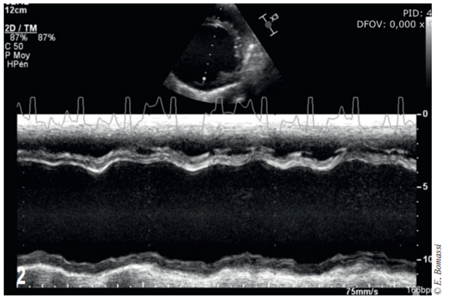

• Un examen echocardiographique permet d’explorer le souffle cardiaque et le bruit de galop. Il met en évidence une dilatation systolo-diastolique et une hypocontractilité ventriculaires gauches (Fig.2), une dilatation atriale gauche, une dilatation ventriculaire et atriale droite, une hypertension pulmonaire systolique, une insuffisance mitrale significative et une insuffisance tricuspidienne modérée (Tab. 1). Un discret épanchement péricardique est objectivé.

photo 2

2 – Échocardiographie à l’admission. Coupe petit axe transventriculaire mode temps-mouvement, obtenue par un abord parasternal droit : dimensions ventriculaires augmentées en systole et diastole, diminution de la contractilité (Tab. 1)